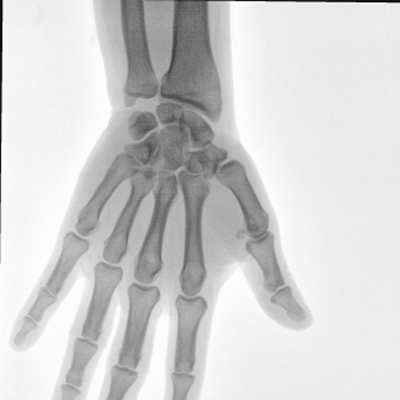

大尺寸動(dòng)態(tài)平板探測器,高DQE、低噪聲、圖像清晰。采用多分辨率圖像增強處理技術(shù),不同部位不同圖像處理算法,滿(mǎn)足客戶(hù)多樣化的需求。

圖形化操控界面設計:設有多種人體特征攝影參數,操作簡(jiǎn)便。雙向紅光十字定位系統:實(shí)現無(wú)射線(xiàn)下的高效定位。信息共享:遵循DICOM3.0格式接口,可無(wú)縫對接云PACS系統。